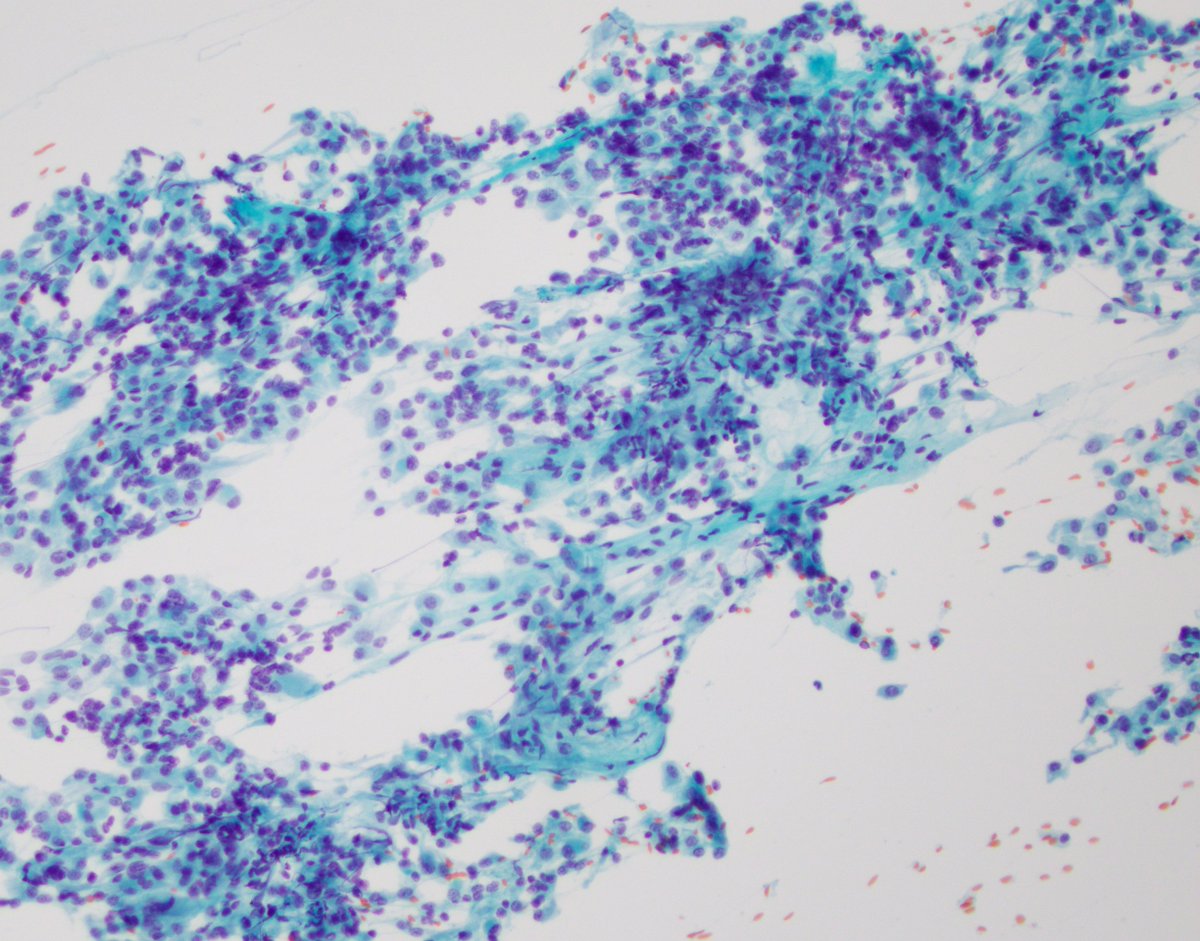

Typical FNA picture of an adenoid cystic carcinoma with uniform basaloid cells, microcystic architecture, and abundant hyaline globules. Check out the new PathologyOutlines.com article on malignant salivary gland FNA! shorturl.at/kKTZ6 #cytopath #ENTPath #FNApath #FNAfriday

Typical FNA picture of an adenoid cystic carcinoma with uniform basaloid cells, microcystic architecture, and abundant hyaline globules. Check out the new <a href="/Pathoutlines/">PathologyOutlines.com</a> article on malignant salivary gland FNA! shorturl.at/kKTZ6 #cytopath #ENTPath #FNApath #FNAfriday